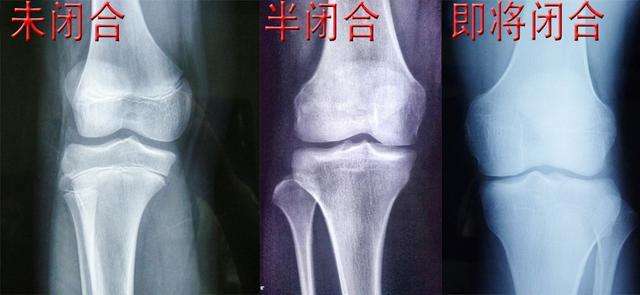

其实,能不能再长高,主要看一个人的骨骺线。指的就是骨骺与干骺端中间的软骨,这个软骨它会因为年龄增长的原因而慢慢骨化,最后变成一条闭合的缝隙,这就是我们所说的骨骺线。

当这个缝隙完全闭合的时候,人的身高也会完全停止生长,如果要看你的骨骺线有无完全闭合,就要去医院拍X光确定。